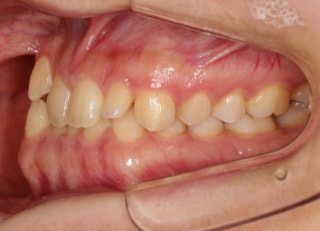

治療前